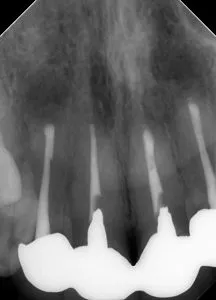

| 術前(写真) | 術後(写真) |

|---|---|

![]() |

| 術名 | 精密根管治療(一回法) |

| 年齢 | 60代 |

| 性別 | 女性 |

| 主訴 | 数ヶ月前から歯ぐきから膿が出ている(他院で歯根破折による抜歯・インプラントを宣告された) |

| 診断名 | 歯内歯周病変(根尖性歯周炎に起因するもの) |

| 治療内容 | ラバーダム防湿下での根管治療、根管充填、支台築造 |

| 治療期間 | 約9ヶ月(治療自体は1日、その後経過観察) |

| 通院回数 | 根管治療自体は1回(その他、経過観察の来院あり) |

| 費用 | 小臼歯 ¥154,000 |

| リスク・副作用 | 歯根破折の程度や歯周病の進行状況によっては、保存が不可能で抜歯が必要になる場合があります。 また、術後に一時的な痛みや違和感が生じることがあります。 |

| 補足事項 | 【診断のポイント】 CT画像にて頬側の骨吸収が確認されましたが、他部位に歯周病がないことや未処置歯(イニシャルトリートメント)であることを踏まえ、 根管治療による骨再生が可能と判断されています。 【経過】 術後1週間でフィステル(瘻孔)が消失し、9ヶ月後にはレントゲン上で骨の完全な再生が確認されました。 |